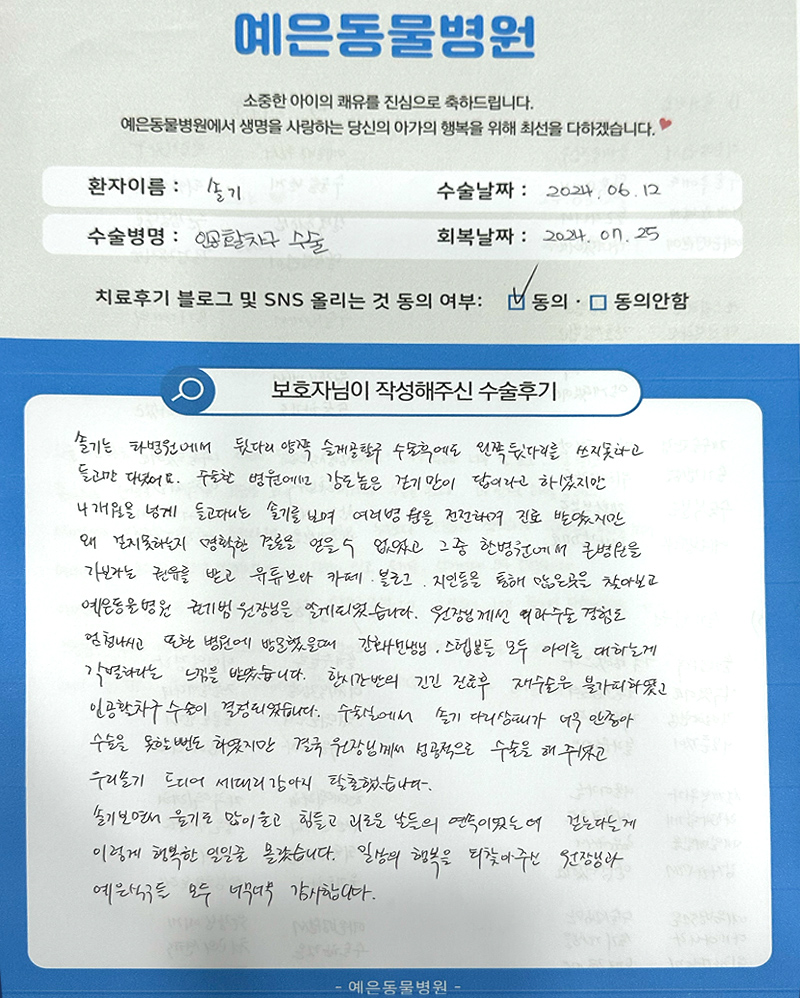

솔기는 타병원에서 뒷다리 양쪽 슬개골 탈구 수술 후에도 왼쪽 뒷다리를 쓰지 못하고 들고만 다녔어요. 수술한 병원에선 강도 높은 걷기만이 답이라고 하셨지만 4개월을 넘게 들고다니는 솔기를 보며 여러 병원을 전전하며 진료 받았지만 왜 걷지 못하는지 명확한 결론을 얻을 수 없었고 그 중 한 병원에서 큰 병원을 가보라는 권유를 받고 유튜브나 카페, 블로그, 지인 등을 통해 많은 곳을 찾아보고 예은동물의료센터 권기범 원장님을 알게되었습니다. 원장님께선 외과수술 경험도 엄청나시고 또한 병원에 방문했을 때 간호사 선생님, 스텝분들 모두 아이를 대하는게 각별하다는 느낌을 받았습니다. 한시간 반의 긴긴 진료 후 재수술은 불가피하였고 인공활차구 수술을 결정하게 되었습니다. 수술실에서 솔기 다리상태가 너무 안좋아 수술을 못할 뻔도 하였지만 결국 원장님께서 성공적으로 수술을 해주셨고 우리 솔기 드디어 세다리 강아지 탈출했습니다. 솔기보면서 울기도 많이 울고 힘들고 괴로운 날들의 연속이었는데 걷는다는게 이렇게 행복한 일일줄 몰랐습니다. 일상의 행복을 되찾아주신 원장님과 예은 식구들 모두 너무너무 감사합니다.